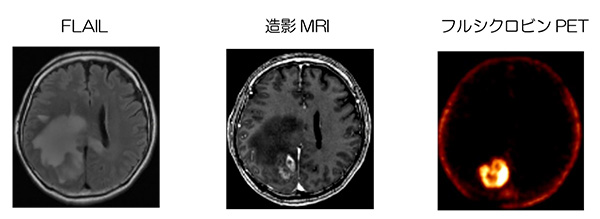

フルシクロビンPET検査は、「初発の悪性神経膠腫が疑われ患者における腫瘍の可視化」し、術前診断に用いられます。

脳腫瘍は、主にMRIでの診断を行いますが、診断ができても、手術時の正常な脳実質と腫瘍は境界が不明瞭なことが多く、腫瘍摘出時の計画時に、正確に摘出範囲や部位が適切に同定できないことがあります。腫瘍細胞では、正常細胞よりアミノ酸代謝が亢進しているため、フルシクロビンがアミノ酸代謝が亢進しているところに集積する性質を利用して、フルシクロビンPET-CTで、悪性神経膠腫の部位をMRIより正確に画像化することで、より正確に摘出範囲を定め、適切な腫瘍摘出計画をたてることができます。

フルシクロビンPETのイメージ

「画像提供日本メジフィジックス株式会社」